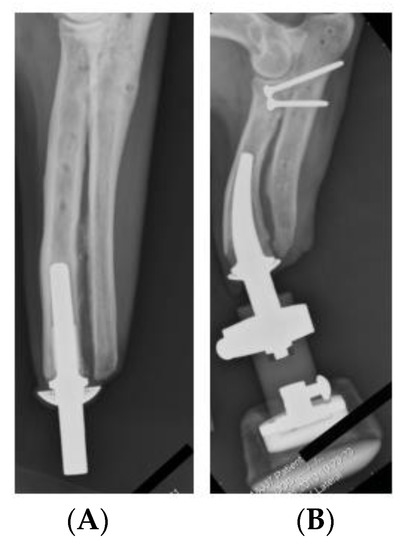

- The ITAP and femur are both cylindrical, where the femur has an outer diameter of 28 mm and is extruded for 311.5 mm. Whilst there is often a curve in the femur, the tensor faciae latae muscle can reduce the stress acting along the bone and therefore reduce any pronounced stress concentrations acting along the femur [18].

- At one end of the femur there is a 14 mm diameter hole, centred in the middle, cut to a depth of 160 mm.

- As the focus of the simulation is on the ITAP, the femur is fixed in place to the pelvis.

- The femur will not be simulated and the free body diagram (FBD) will only consist of the ITAP and the resulting σ is analysed for the impact on the bone anchor.

- The top of Section C joined to Section B of the ITAP (Figure 8B).